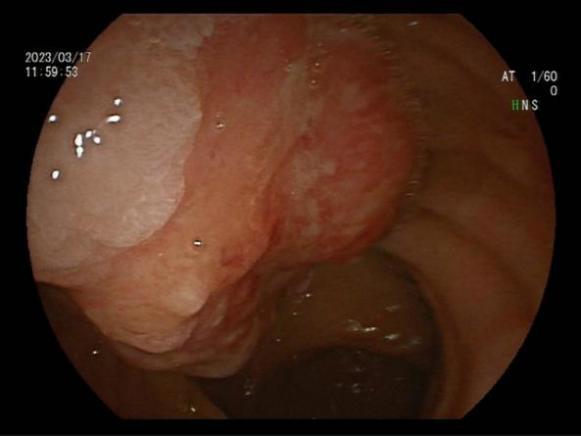

八、内镜下内痔硬化剂及套扎治疗

内镜套扎治疗及硬化治疗 适合I-III期 内痔,包括部分混合痔的微创治疗,疗效显著,与传统外科手术相比,超级微创、费用低、见效快,具有很大优势。

III度内痔 硬化剂及套扎术后